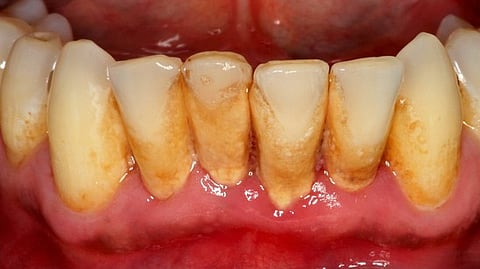

Gum disease is caused by bacterial infection and inflammation of the gums and surrounding tissues. It typically begins with gingivitis, characterized by red, swollen gums that may bleed during brushing or flossing. If left untreated, gingivitis can progress to periodontitis, a more severe form of gum disease that can lead to irreversible damage to the gums and bone that support the teeth.

Scaling and Root Planing: Scaling and root planing is a non-surgical procedure that involves removing plaque and tartar from the surfaces of the teeth and below the gumline, smoothing out rough spots on the roots of the teeth to prevent bacteria from accumulating.